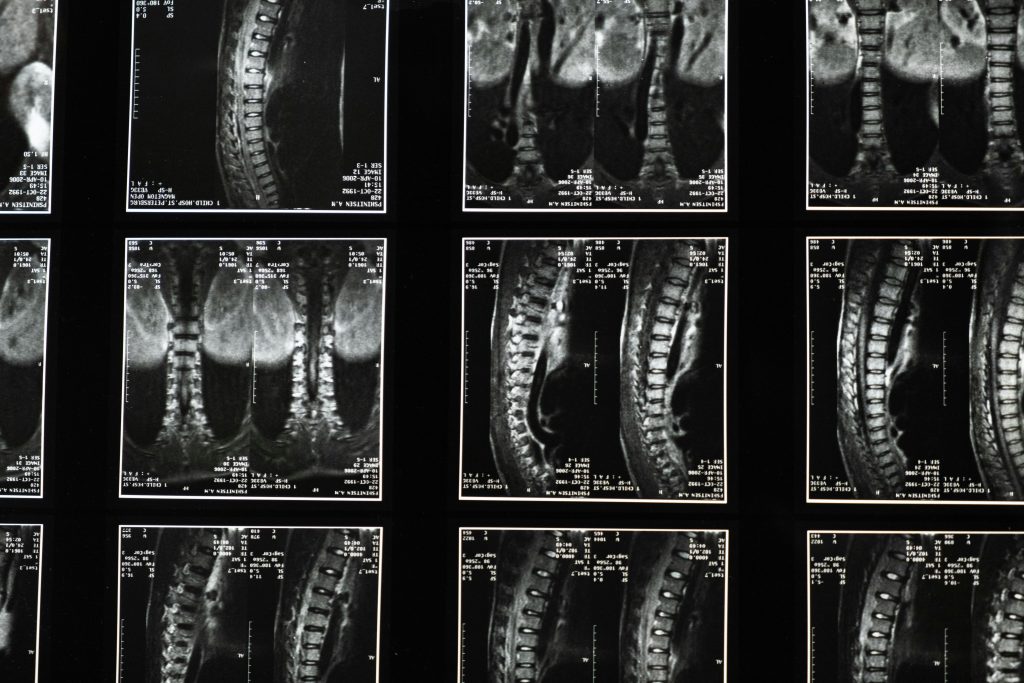

- Imaging Tests: MRI or CT scans visualize spinal structures, revealing herniated discs, spinal stenosis, or other abnormalities.